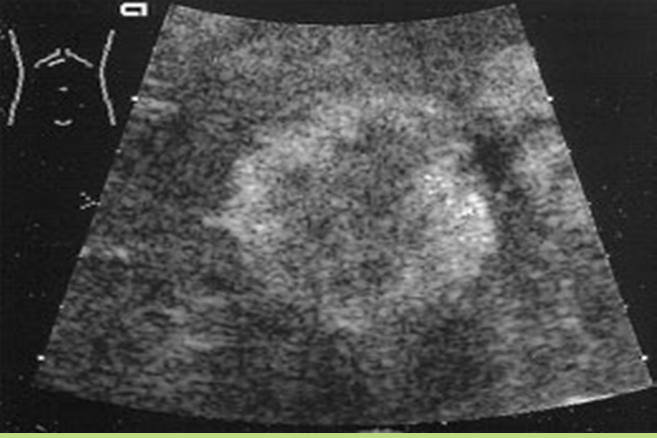

May also present

wheel within a wheel

Bull's eye

Echogenic focus

Candidiasis

early wheel within wheel

later hypoechoic